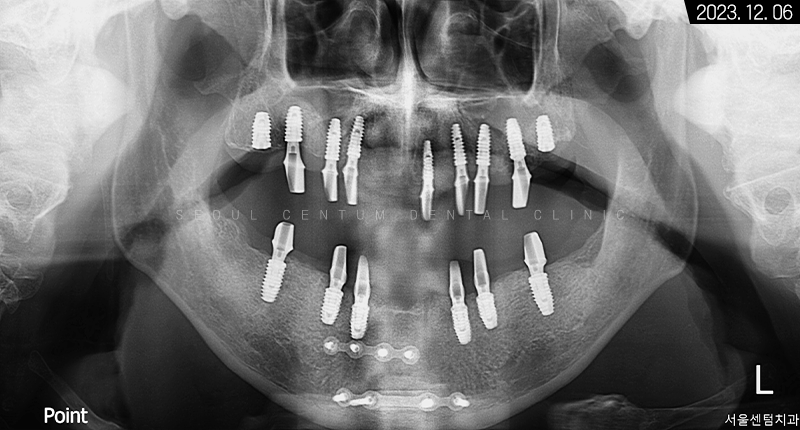

그렇게 약 9개월의 전체임플란트 기간을 들여서 완성된 모습을 만날 수 있었는데요. 골융합을 높이기 위해 네오 브랜드와 폰틱을 결합하여 사용했습니다.

임플란트를 하면서 심미적으로 보완이 되었고 지르코니아를 수복함에 따라 깍두기, 나물, 고기처럼 질기거나 딱딱한 편의 음식을 예전보다 마음껏 드실 수 있게 되었습니다. 뼈 이식술도 동반했기에 픽스처가 더 힘을 잘 받을 수 있게 됐습니다.

3개월이 더 지난 후 치근단 사진과 파노라마 엑스레이 사진으로 살펴봐도 초기 임플란트 식립 상황과 동일하게 견고히 자리 잡아 있는 것을 볼 수 있었습니다. 주위염도 생기지 않아 이상적인 결과를 만들어볼 수 있었어요.

전체임플란트 기간 동안 환자분께서 상당히 불편하고 힘드셨을 텐데 잘 이겨내 주셔서 교합도 이상적으로 맞물렸습니다. 아주 마음에 들어 하신 만큼 저희도 보람찼던 임플란트 풀케이스 사례였습니다^^